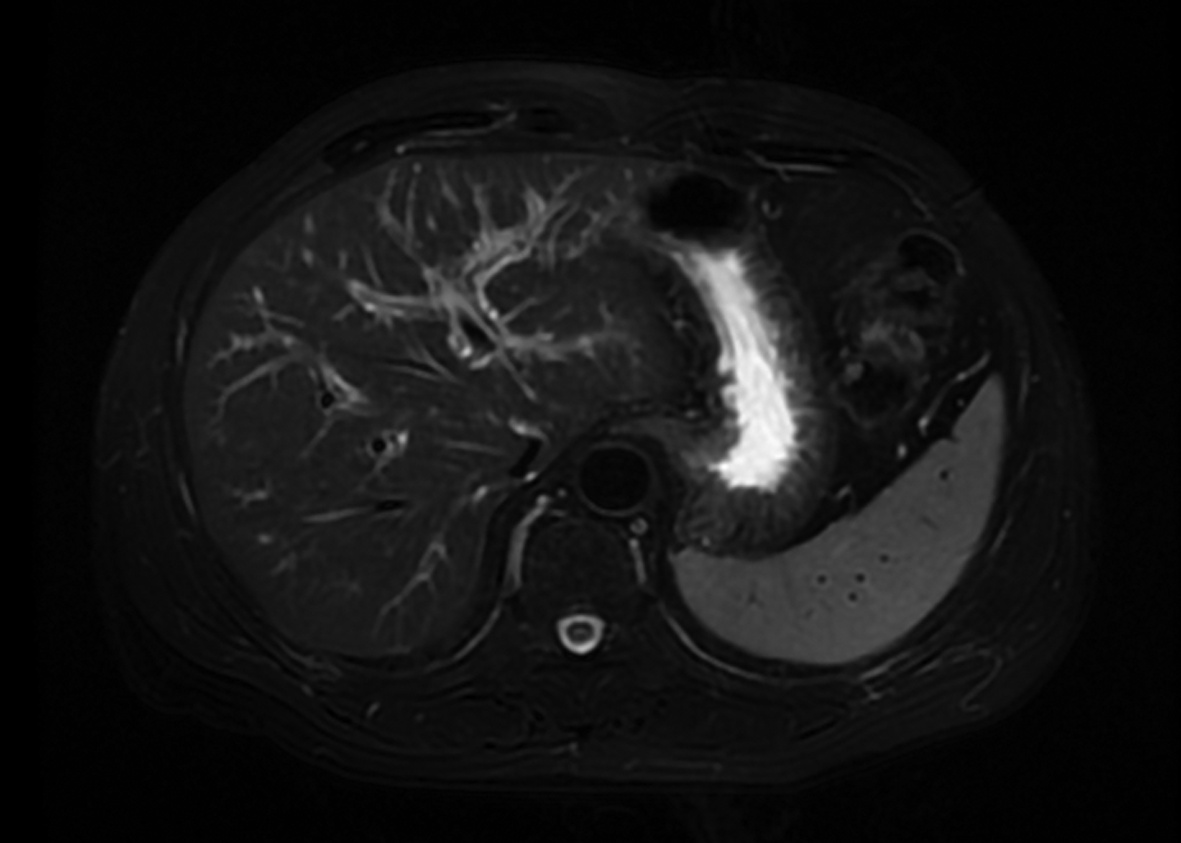

肝移植术后自发性肝破裂出血1例报告

马健, 何力宏, 王凌云, 翟亚楠, 李汛, 张磊

2022, 38(4): 891-893. DOI: 10.3969/j.issn.1001-5256.2022.04.030

摘要(1066) HTML (365) PDF (3041KB)(58)

摘要: